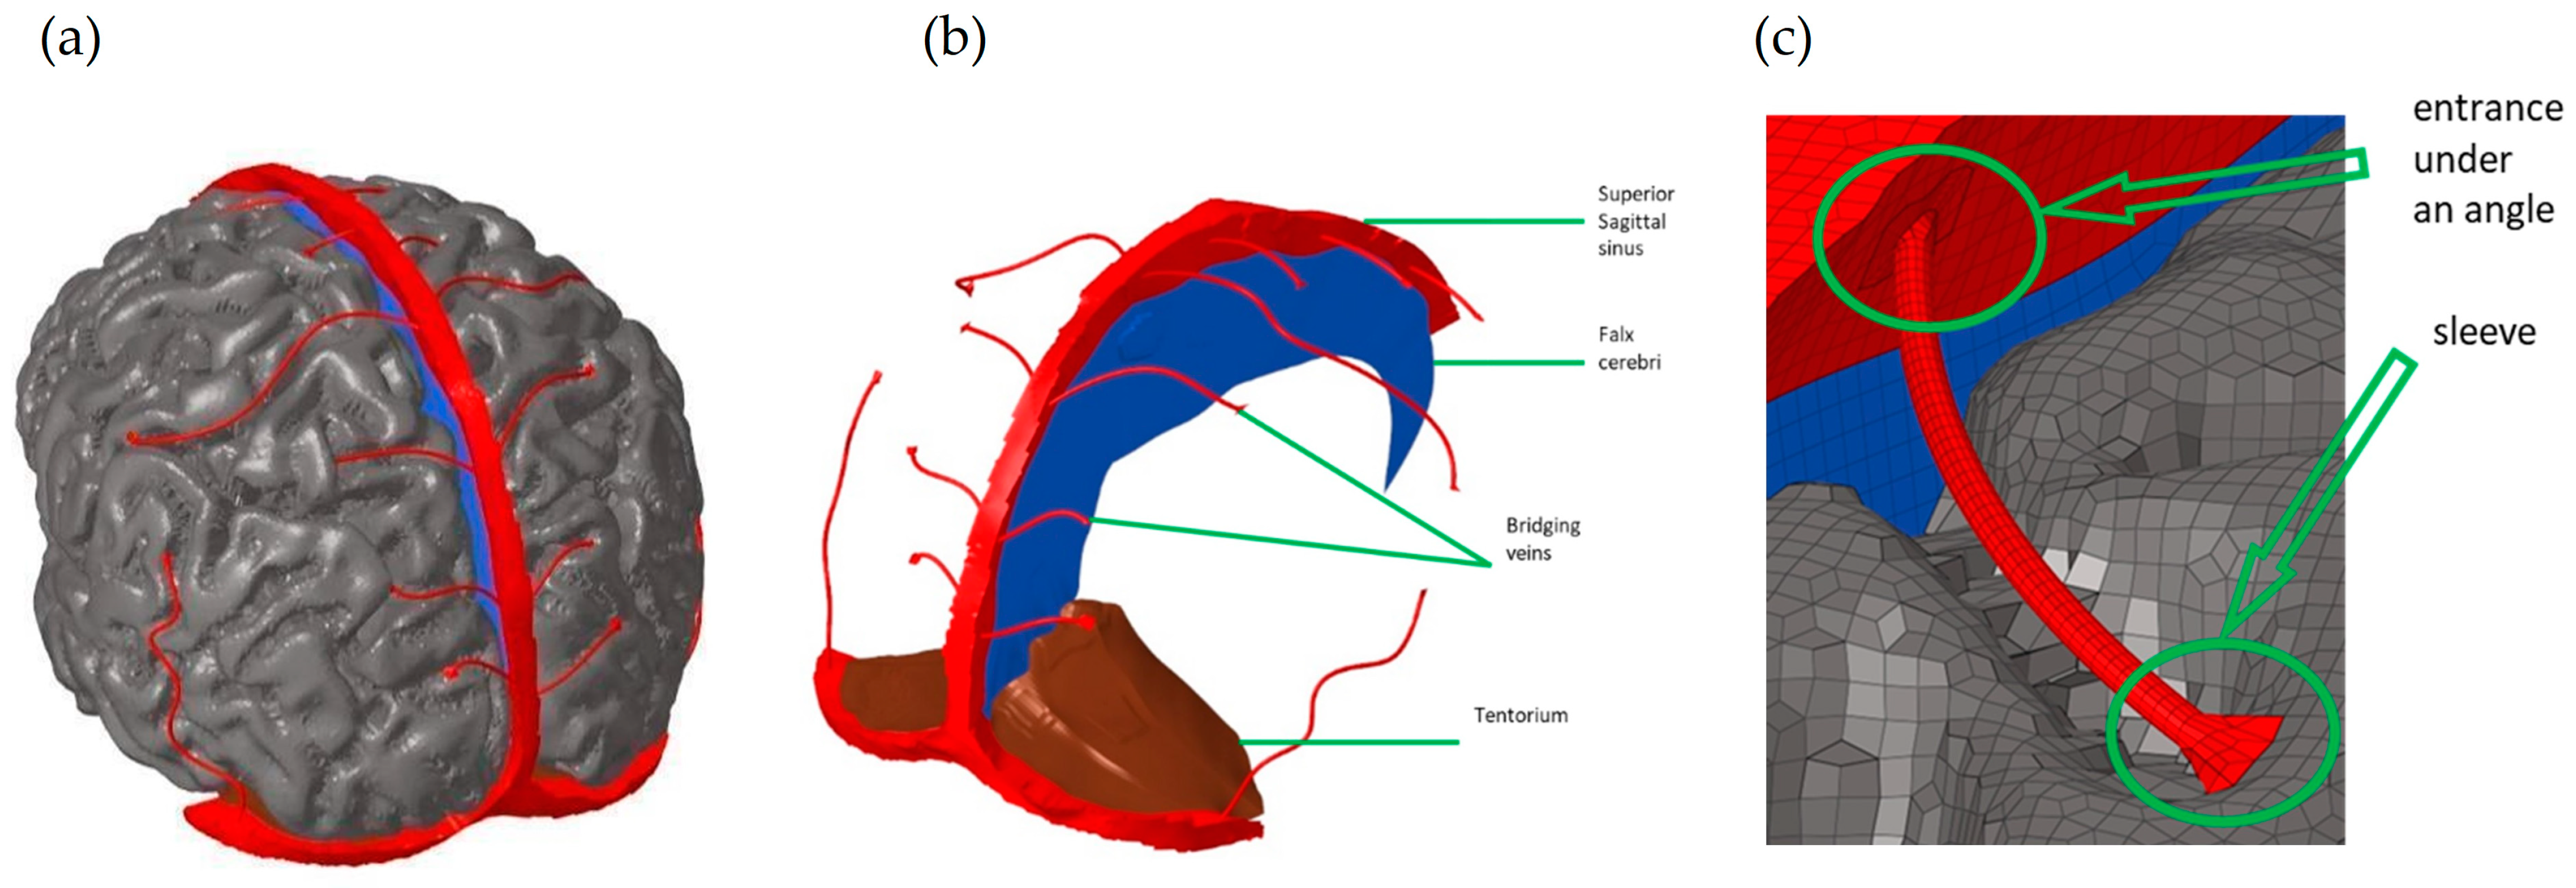

2.2. Development of the Human Head Numerical Model

2.3. Model Geometry

| Structure | Reference | Density [t/m3] | Young’s Modulus or Bulk Modulus [MPa] | Other Material Parameters | Type No. of FEs | Image of Structure |

|---|---|---|---|---|---|---|

| White matter—left/right hemisphere | THUMS MAT_VISCOELASTIC 2 [35] | 1.00 × 10−9 | Bulk modulus 2.16 × 10−3 | G0 = 12.5 × 10−3 G1 = 6.125 × 10−3 | hexa 231,146/ 237,494 |   |

| Grey matter—left/right hemisphere | THUMS MAT_VISCOELASTIC 2 [35] | 1.00 × 10−9 | Bulk modulus 2.16 × 10−3 | G0 = 10 × 10−3 G1 = 5 × 10−3 | hexa 313,176/ 311,954 |   |

| Cerebellum brainstem | F.A.O. Fernandes et al., 2018 [30] | 1.04 × 10−9 | – | Ν = 0.49999 Mu1 = 0.0012 Alpha1 = 5.05007 | hexa 204,567 |  |

| Pia mater | LLC Elemance—GHBMC Model 2014; M. Ratajczak et al., 2019 [32,34] | 1.13 × 10−9 | 31.5 | ν = 0.45000 | shell 245,632 |  |

| Dura mater | LLC Elemance—GHBMC Model 2014; M. Ratajczak et al., 2019 [32,34] | 1.13 × 10−9 | 31.5 | ν = 0.45000 | shell 92,152 |  |

| Falx cerebri | LLC Elemance—GHBMC Model 2014; M. Ratajczak et al., 2019 [32,34] | 1.13 × 10−9 | 31.5 | ν = 0.45000 | shell 1197 |  |

| Tentorium cerebelli | LLC Elemance—GHBMC Model 2014; M. Ratajczak et al., 2019 [32,34] | 1.13 × 10−9 | 31.5 | ν = 0.45000 | shell 1669 |  |

| Superior sagittal sinus and transversal sinus | LLC Elemance—GHBMC Model 2014; M. Ratajczak et al., 2019 [32,34] | 1.04 × 10−9 | 28.2 | ν = 0.45000 | shell 10,627 |  |

| Bridging veins | Monea et al., 2014 [31] | 1.13 × 10−9 | 30 | 0.48000 | shell 10,627 |  |

| Cerebrospinal fluid (CSF) | DYNAmore GmbH 2018; Gomez-Gesteira et al., 2012 [32,36] | 1 × 10−9 | – | viscosity coefficient 7 × 10−10 | SPH 191,406 |  |